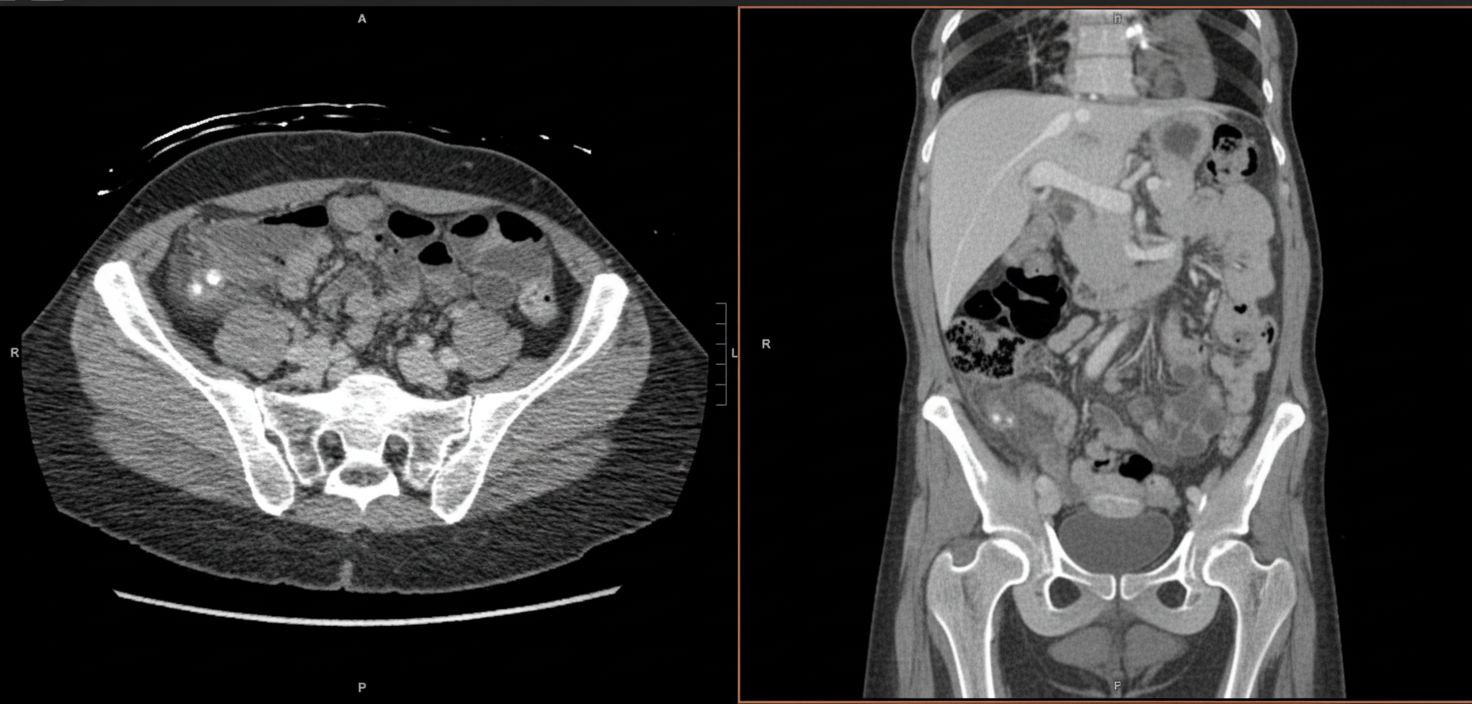

A 27-year-old woman presents with high fever and abdominal pain. Initially, the pain is around the navel but shifts to the right lower quadrant. A CT scan is provided. Which structure is affected?

Explanation: ***Appendix*** - Classic presentation of **periumbilical pain** migrating to the **right lower quadrant (McBurney's point)** with fever strongly indicates **acute appendicitis**. - CT findings typically show **appendiceal wall thickening >6mm**, **periappendiceal fat stranding**, and possible **appendicolith** or fluid collection. *Right ovary* - **Ovarian pathology** (torsion, cysts) typically presents with **sudden onset pelvic pain** without the characteristic pain migration pattern. - Usually lacks **systemic signs** like high fever and **Rovsing's sign** (pain in RLQ when palpating LLQ) seen in appendicitis. *Ileocecal junction* - **Ileocecal pathology** (Crohn's disease, intussusception) presents with **crampy abdominal pain** and **diarrhea**, not the classic appendicitis pain pattern. - CT would show **bowel wall thickening** at the junction rather than isolated appendiceal inflammation with fat stranding. *Ascending colon* - **Ascending colon pathology** typically presents with **right-sided abdominal pain** that is more diffuse and associated with **bowel symptoms**. - CT findings would show **colonic wall thickening** or **diverticular changes** rather than the focal appendiceal inflammation seen in appendicitis.